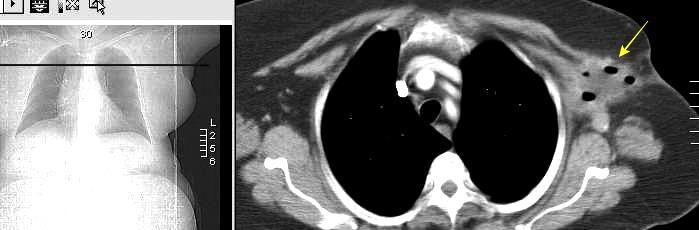

Pliegue axilar Normal

Rehúsa cirugía

2011. Acude por masa axilar

Linfoma NH de cél. B. Invasión Transtorácica.

Afectación axilar